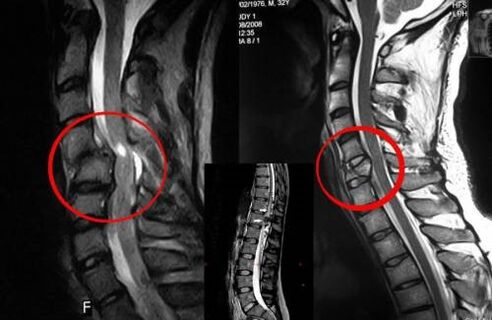

Diagnose

Eine Wirbelosteochondrose erfordert eine rechtzeitige Konsultation eines Arztes, der bei der Wiederherstellung des geschädigten Rückens hilft. Moderne Geräte ermöglichen eine Diagnose bereits in frühen Entwicklungsstadien. Im Falle einer Pathologie wenden Sie sich an einen Neurologen oder Orthopäden. Zunächst wird eine Untersuchung der verletzten Wirbelsäule durchgeführt und eine Anamnese erhoben, anschließend werden labor- und instrumentelle Diagnosemethoden verordnet, die eine Osteochondrose erkennen:

- Röntgen;

- Myelographie;

- neurologische Untersuchung;

- CT und MRT;

- Kernspinresonanz.